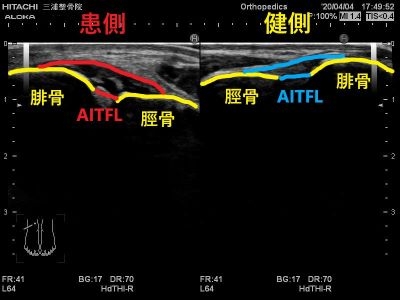

エコーではこのように写ります。

患側では大きく腫れて

正常な靭帯線維が見えないため

二分靭帯が断裂しています。